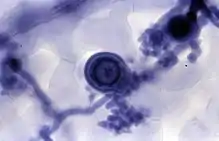

It may be used to observe fungal hyphae[6] and stramenopiles.